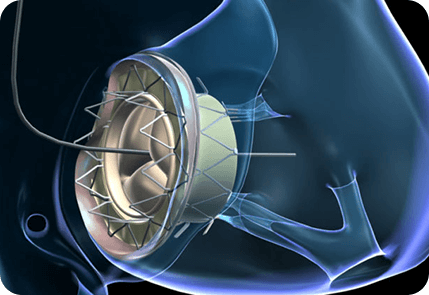

下图为手术治疗瓣膜:

-

介入治疗

经导管主动脉瓣置换术(Transcatheter Aortic Valve Replacement, TAVR)